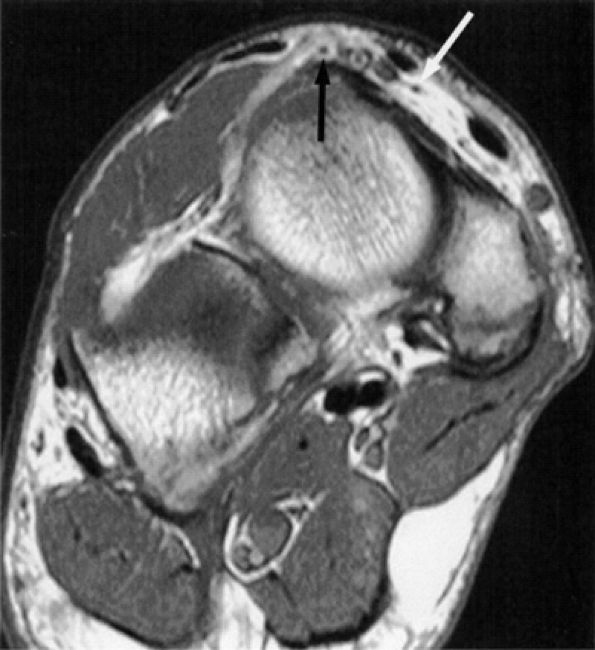

FIGURE 6.3 ● Proximal tibial entrapment in a 49-year-old patient with neuropathic foot pain. Symptoms resolved following an intra-articular steroid injection of the knee. This axial T2-weighted fat-suppressed image depicts a loose body in the popliteal muscle bursa (arrow), abutting on the neurovascular structures (arrowheads).There are many variations in muscle innervation and many communicating nerve loops in the lower extremity, particularly in the foot region.43 For example, the deep peroneal nerve may, in rare instances, supply muscles such as the adductor hallucis and flexor hallucis brevis, muscles typically innervated by the lateral and medial plantar nerves. This variability can affect the distribution of signal alterations within denervated muscles and may produce puzzling MR patterns. Familiarity with variations in innervation aids in interpreting unexpected muscle denervation signal alterations. -

Finally, the distance from the site of entrapment to the innervated muscle should be considered when searching for muscle denervation abnormalities. Proximal damage to the peroneal division of the sciatic nerve may depict denervation signal in the leg or foot. This signal alteration may be missed if only the thigh is being imaged. Similarly, MR imaging of a painful foot may overlook a more proximal entrapment in the leg or thigh (Fig. 6.3). It is important to pay careful attention to signal changes on sagittal and coronal planes, where larger portions of the limb are illustrated, to help avoid this pitfall. If the clinical suspicion for entrapment is high and no abnormalities are noted on the initial study, imaging a more distal or proximal section of the limb can also be performed.